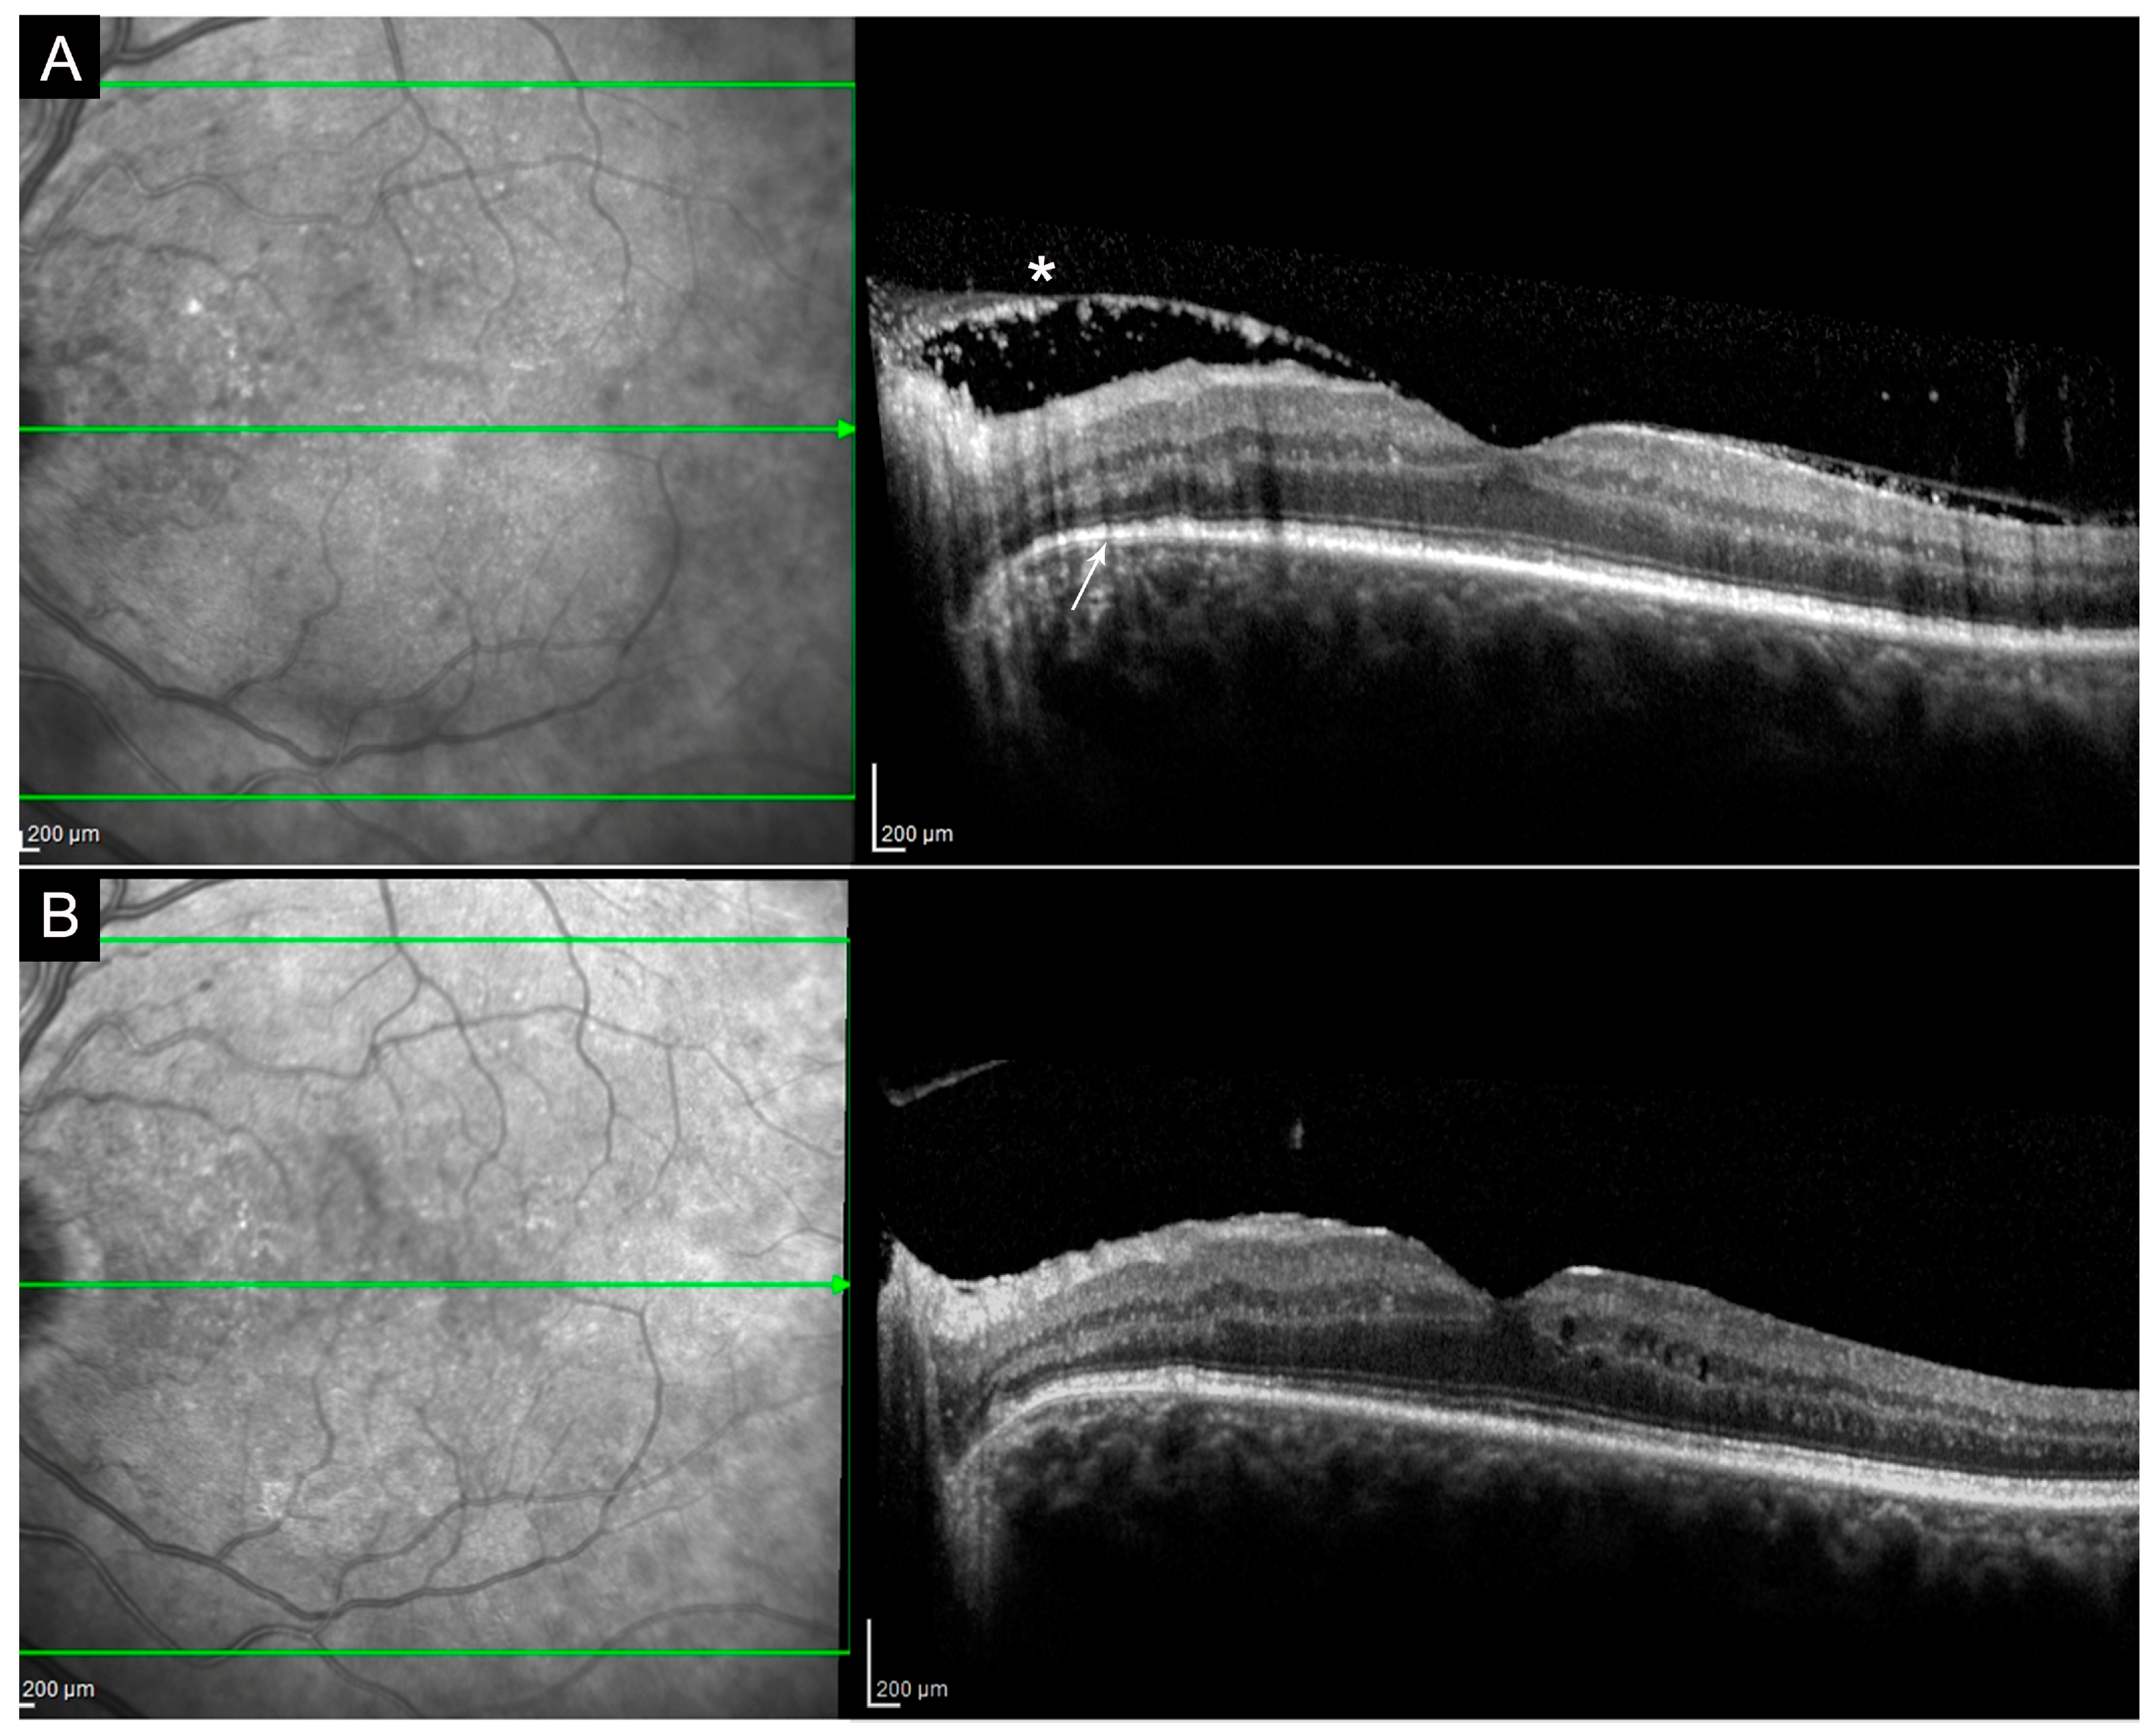

2.1. Syphilis

- Cavallero, E.; Pirani, V.; Cesari, C.; Carrozzi, G.; Giovannini, A.; Mariotti, C. Multimodal Imaging Analysis of Acute Syphilitic Posterior Placoid Chorioretinitis: A Case Report. Ophthalmic Surg. Lasers Imaging Retina 2019, 50, e179–e184. [Google Scholar] [CrossRef]